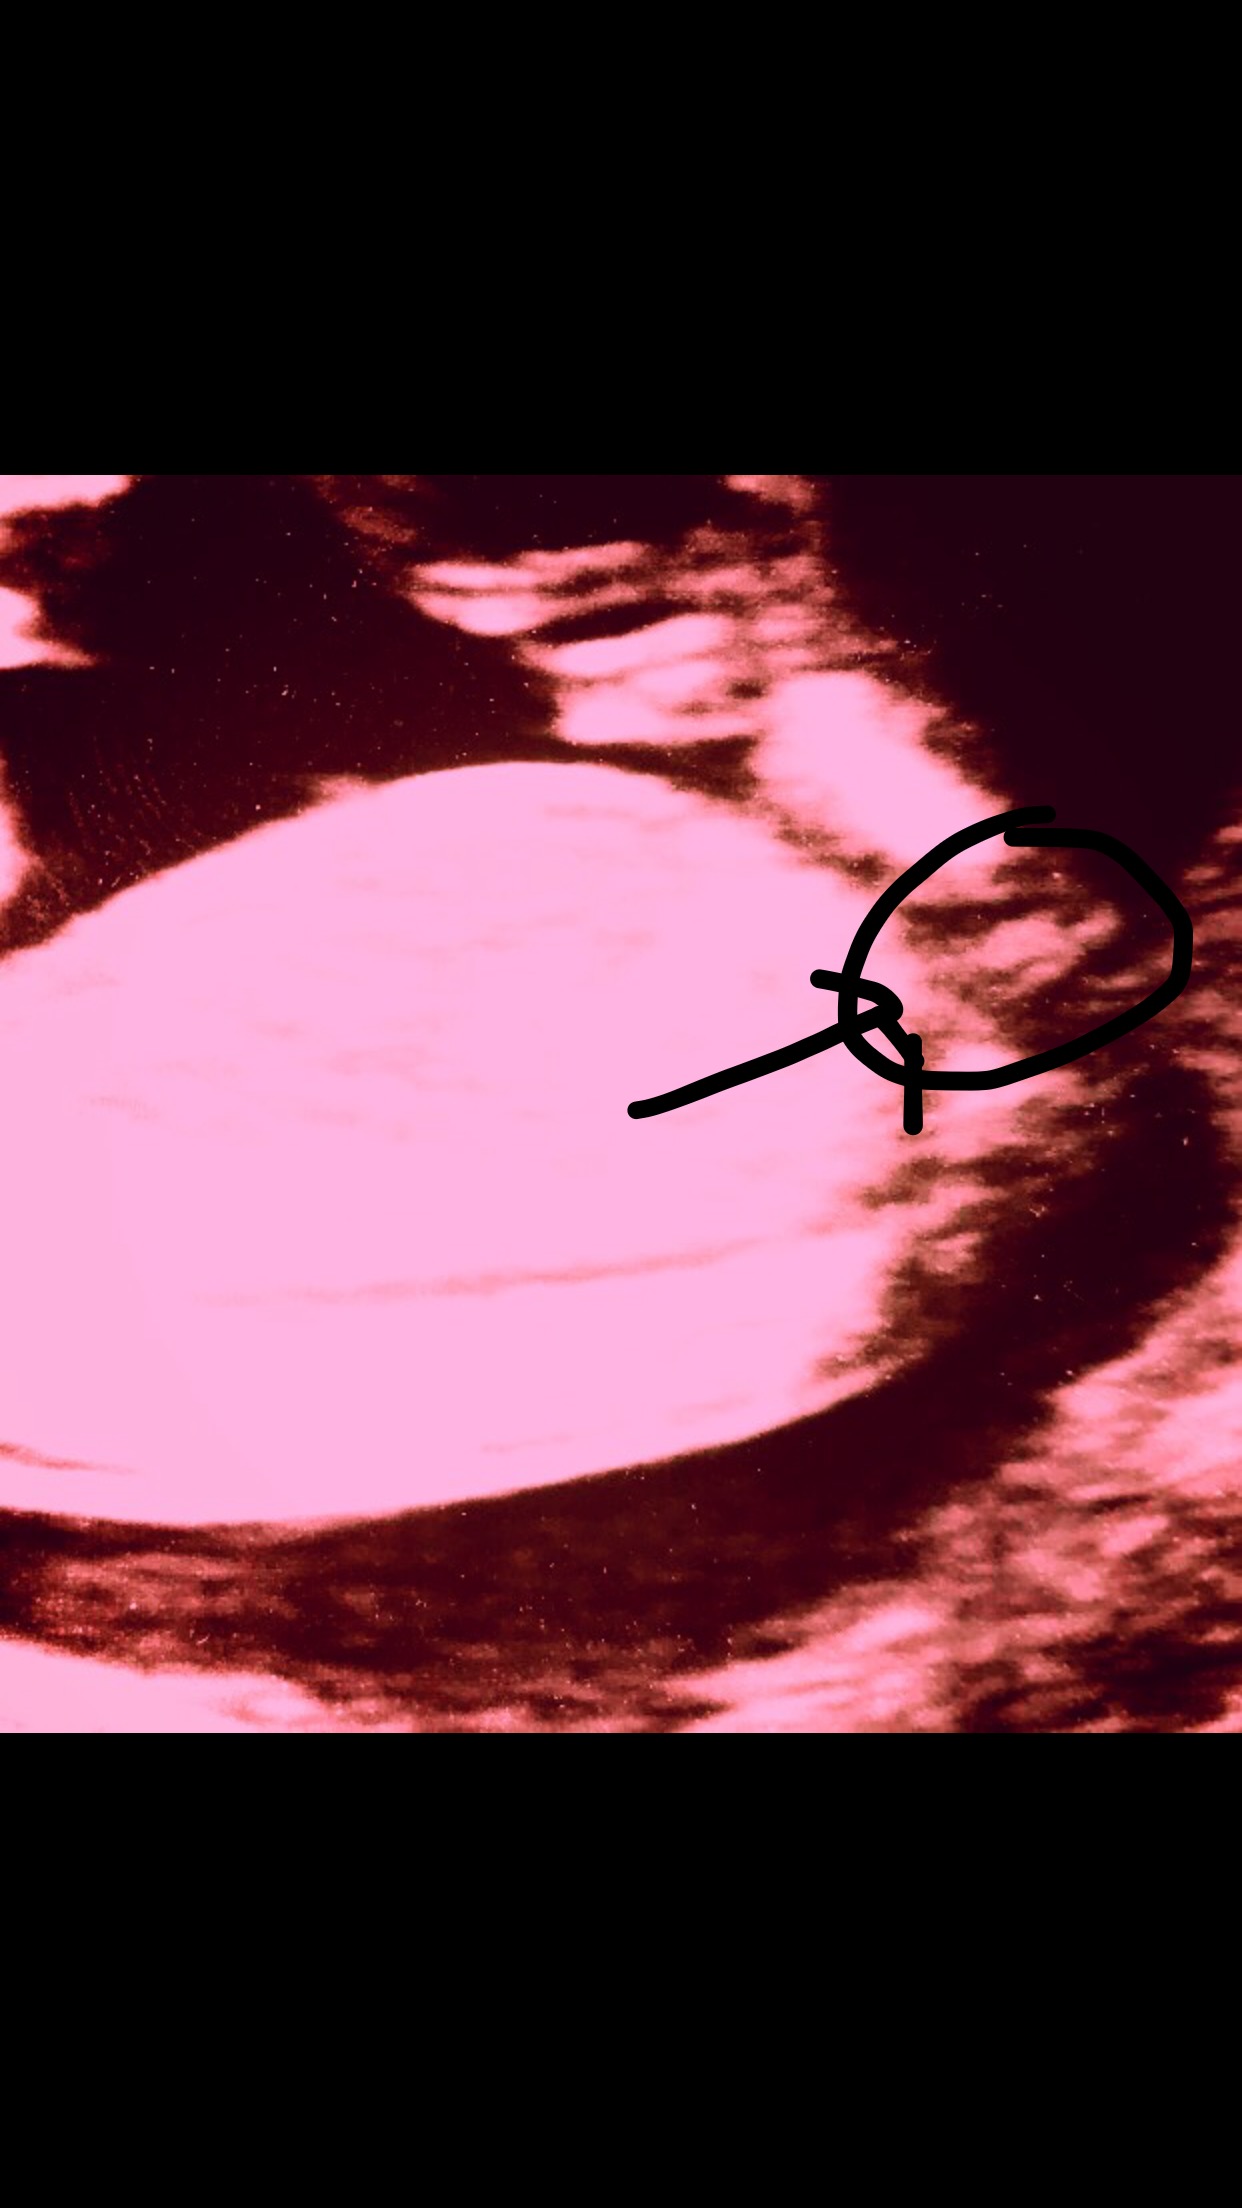

Can anyone guess the sex from the nub? I'm thinking there's stacking?

I should add the baby is 13 weeks 6 days. Thanks

I have only one other that I don't think shows a nub but I will include the 12 week scan that is red, I changed the colour so I could see what the bright white line was more clearly. Attachment 37544Attachment 37545